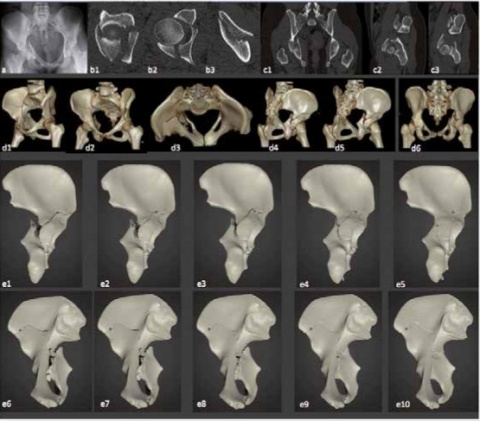

A: herkömmliche Röntgentechnik, b1-b3: CT (seit 1973 möglich), c1-c3: Multiplanare Rekonstruktion (seit 1993 möglich), d1-d6: 3D-Rekonstruktion

(seit 1993 etabliert), e1-e10: 3D-Druck (seit ca. 2013 in der Unfallchirurgie); Animation der Reposition durch komplexe Slicing Software

und Unity 3D-Software (seit 2017/2018 ist die Darstellung für den Nutzer auch als Video möglich) (Bilder: C. Willy, Berlin)

(PLA) im Fused-deposition modeling (FDM)-Extrusionsverfahren (Bilder: T. Pulpanek, Berlin)